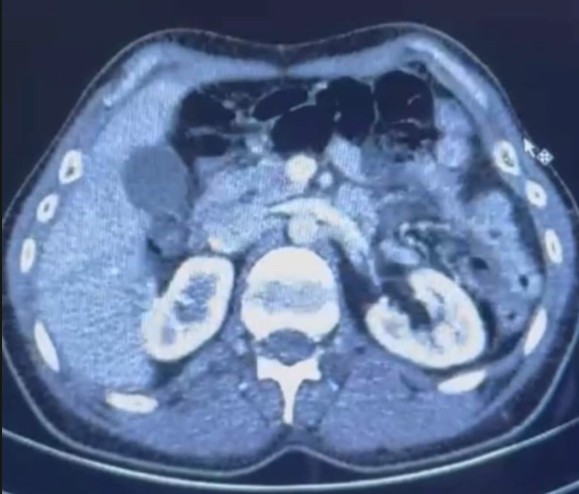

Şüphelilerin üzerlerinde ve çevrelerinde yapılan kontrollerin ardından, S.C. ve R.B.C. Kayseri Şehir Hastanesine sevk edilerek iç beden muayenesi yapıldı. Muayenede iki şahsın mide bölgesinde 50 adet kapsül şeklinde toplam 554 gram uyuşturucu madde bulundu.